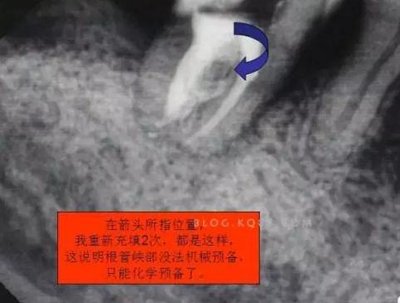

1.拍片基本可以確定遠(yuǎn)中頰側(cè)根管是一個(gè)融合根管,也就是常見的C型根管,粗大的根管口是扁形,根管同樣呈扇貝型,根尖孔粗大。而且在根管中上段較粗大,插針拍片后遠(yuǎn)中顯示根管有側(cè)穿的可能,但是通過內(nèi)窺鏡顯示是沒有任何側(cè)穿點(diǎn),也沒有滲血和患者有疼痛現(xiàn)象。這個(gè)病例告訴我們,有時(shí)候做根管治療,為了把根管做通和預(yù)備到位,必要的牙體組織去除是可以的,后期可以用冠修復(fù)來彌補(bǔ),如果不去除,本病例的根管治療,根充時(shí)可能會(huì)面臨充填不嚴(yán)密,從而導(dǎo)致根管治療的失敗,這是不可取的。

3.開髓去腐后,髓腔基本就是這樣,在頰側(cè)近遠(yuǎn)中都有根管口顯示,初步用8號(hào)C+銼去試探性探查根管,沒有阻力感,以為就是c型根管,舌側(cè)用C+銼時(shí)有阻力感覺,接上測(cè)量?jī)x去探查根管,以防C+銼探通后超出根尖孔,最后舌根長(zhǎng)度16mm*15號(hào)K銼(16.5mm*8號(hào)C+銼),機(jī)擴(kuò)F2。接下來著重頰側(cè)的根管尋找,后來在頰側(cè)近遠(yuǎn)中插入K銼時(shí)總覺得K銼尖段都指向一個(gè)位置,感覺不對(duì),再次讀X線片,后來發(fā)現(xiàn)術(shù)前沒有仔細(xì)查看X線片,以及未回顧這位患者年齡,也就忘記牙齒的增齡性改變的含義。髓腔之所以小或者不清楚,一個(gè)因?yàn)槟挲g增加的原因二是因?yàn)檠例X長(zhǎng)期受到外界物理化學(xué)刺激所導(dǎo)致髓腔變小,甚至沒有髓腔顯影。本病例患者,髓腔有大概顯影,但髓室里好像有增生的牙體組織,其實(shí)就是髓石。并且和髓室底相連接。如果不注意,有可能按常規(guī)預(yù)備方法進(jìn)行預(yù)備。